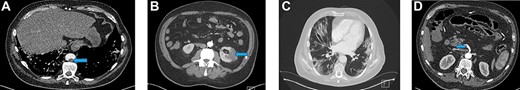

Blood investigations showed an elevated WCC, a low lymphocyte count and elevated CRP. His prothrombin and thrombin times were also prolonged (Table 1). A CT scan demonstrated filling defects in the descending thoracic and abdominal aorta (Fig. 2A) and superior mesenteric artery (SMA) suggestive of acute thromboembolic phenomena. There was no sign of ischaemic bowel. A wedge-shaped peripheral hypodensity was seen at the mid-pole of the left kidney (likely to be a renal Infarct) (Fig. 2B). A CT of the chest showed patchy and ground-glass shadowing (Fig. 2C).

(A) Filling defect in aorta (blue arrow). (B) Left renal infarct (blue arrow). (C) CT-thorax showing pulmonary changes. (D) Thrombus in the distal SMA (blue arrow)